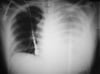

Рентгенография грудной клетки

Гемоторакс подозревается на основании симптоматики и данных физического обследования. Диагноз, как правило, подтверждается с помощью рентгенографии органов грудной клетки и иногда E-FAST или КТ.

Если объем крови достаточный, чтобы быть визуально заметным при рентгенографии грудной клетки (обычно необходим объем примерно 500 мл), или если присутствует пневмоторакс, проводят введение зонда большого калибра (например, от 28 до 38 по французской шкале диаметров катетера) в пятое или шестое межреберье на уровне средней подмышечной линии. Зондирование улучшает вентиляцию, уменьшает риск свернувшегося гемоторакса (который может привести к развитию эмпиемы или фиброторакса) и облегчает оценку текущей кровопотери и диафрагмальной целостности. Кровь, собранная с помощью зондовой торакостомии, может быть использована для аутотрансфузии, что снизит потребность в кристаллоидах и экзогенной крови.